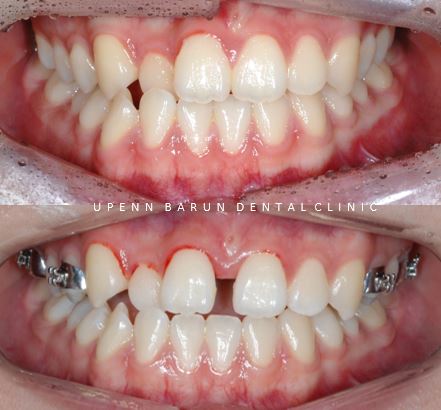

Case 3

세번째 환자분도 타치과에서 교정치료를 시작후

개인적인 이유로 저희병원에 내원해주셨습니다.

치료기간 22.12 ~ 23.8

어금니쪽 반대교합이 있었고

악궁이 좁아있던 왼쪽 사진과 달리

'Marpe'장치 후 악궁이 상당히 넓어졌습니다.

'Marpe' 악궁확장은 가운데 중심선인

정중구개봉합선을 분리 시켜 상악의 너비를 넓혀줍니다.

악궁확장을 통해 앞니 사이의 공간을 얻은 후

치아를 재배열 하기 위한 단계를 거쳐

마무리 해드릴 예정입니다^^